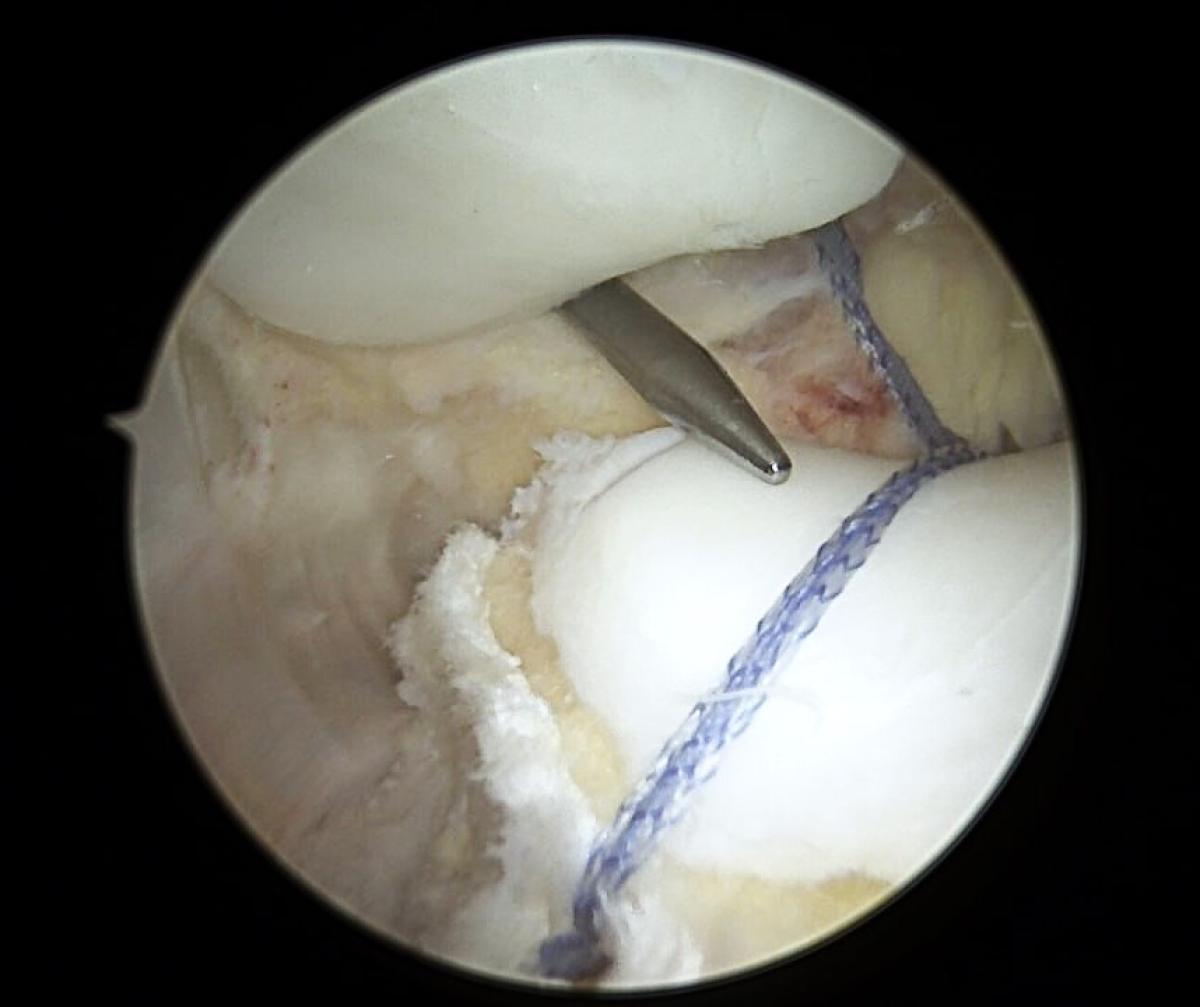

Гэмтэл согог судлалын үндэсний төвийн салбар эмнэлгийн Спортын гэмтлийн төвийн эмч нар Монголд анх удаа дунд чөмөгний булууны дутуу хөгжлийг дурангийн мэс заслын аргаар эмчлэх шинэ технологийг тусламж үйлчилгээнд нэвтрүүллээ.

Энэхүү мэс засал эмчилгээ нь дунд чөмөгний булууны хүнхэрийн хүнд хэлбэрийн дутуу хөгжил, гажиг согогийн шалтгаант тойгны архаг тогтворгүйтэл, мултралыг дурангийн мэс заслын аргаар эмчлэх дэвшилтэт арга технологи юм.

Одоогийн байдлаар, тус мэс засал эмчилгээнд 21-25 насны дөрвөн үйлчлүүлэгч хамрагдсан бөгөөд эмчилгээний үр дүн сайтай байгаа юм.